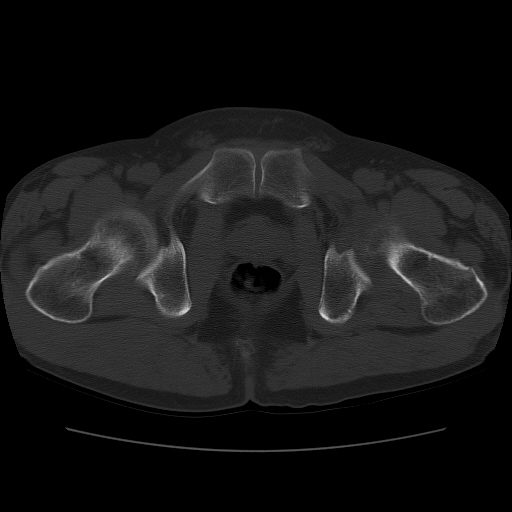

标题: CT11650:左髋病变,请会诊.

左髋疼痛不适近半年,局部无红肿热.无明确外伤病史.黄酒每天二餐.

考虑左侧股骨头缺血性坏死.(常期饮酒引起代谢障碍?)

左侧股骨头缺血性坏死;很典型。

“局部无红肿热.无明确外伤病史.黄酒每天二餐”。考虑左侧股骨头缺血性坏死。